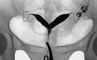

Исследование чаще проводят на 7—19-й день после окончания менструации в положении женщины для гинекологического исследования. После обработки влагалища и шейки матки спиртовым раствором йода в канал шейки матки вводят маточную канюлю, через которую в полость матки медленны под контролем рентгеноскопии вводят 10—12 мл 60—76% раствора водорастворимого рентгеноконтрастного вещества (урографина, уротраста, гипака и др.), температура которого равна 36—37°. По мере заполнения полости матки и маточных труб производят рентгенографию. Если на рентгенограммах через 3—5 мин не отмечается заполнения маточных труб, через 20—25 мин делают повторные снимки. По рентгенограммам оценивают состояние канала шейки матки, положение матки, конфигурацию и размер ее полости, расположение и проходимость маточных труб (рис. 1 и 2).